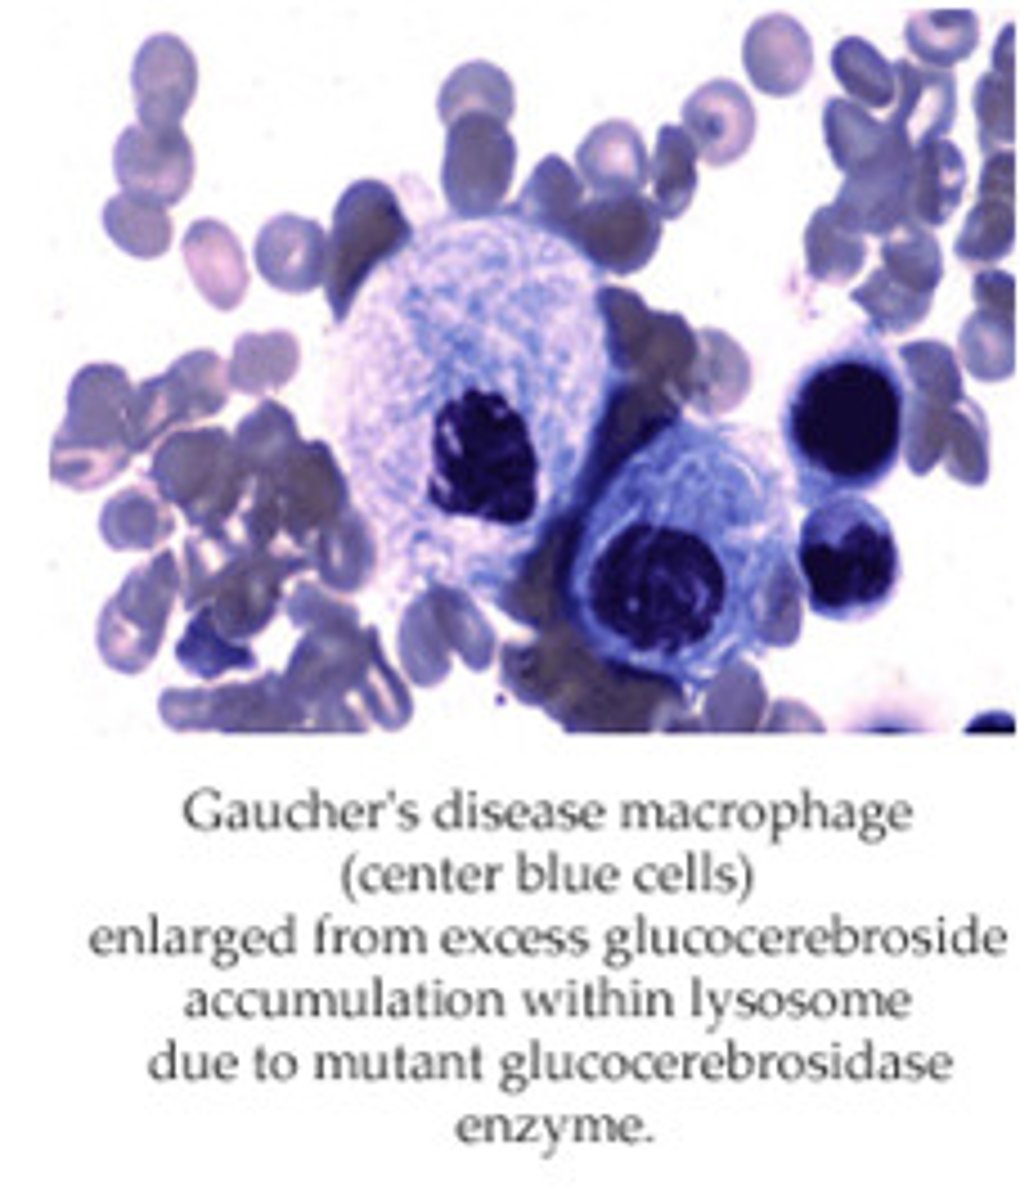

Hepatosplenomgaly, pancytopenia, osteoporosis, aseptic necrosis of femur, bone crises in child

Gaucher disease macrophage (glucocerebrosidase deficiency)

#1 lysosomal storage disease

Build up of glucocerbroside

"Crinkled tissue paper cells"